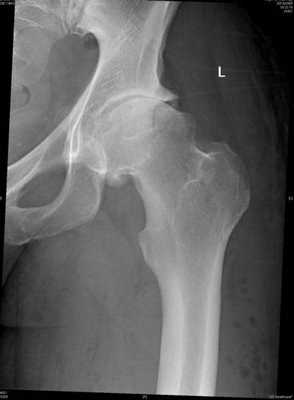

- Кэм-тип. Первоисточник импинджмента - анормальная форма бедренной кости в проксимальной части с утратой сферичности при неизмененном вертлюжном углублении. В 14 раз чаще такая проблема встречается у пациентов мужского пола. Возрастная группа больных - 21-50 лет. Снимки рентгена в прямой и латеральной плоскости показывают:

- деформацию метаэпифиза бедра по типу «рукояти пистолета»;

- шеечно-диафизарный угол меньше 125°;

- симптом горизонтальной эпифизарной пластины;

- ∠α (альфа-угол) от 50° и более;

- сокращенный offset шейки - ниже 8 мм, offset-индекс менее 0,18;

- отклонение шейки бедра кзади (ретроторсия).